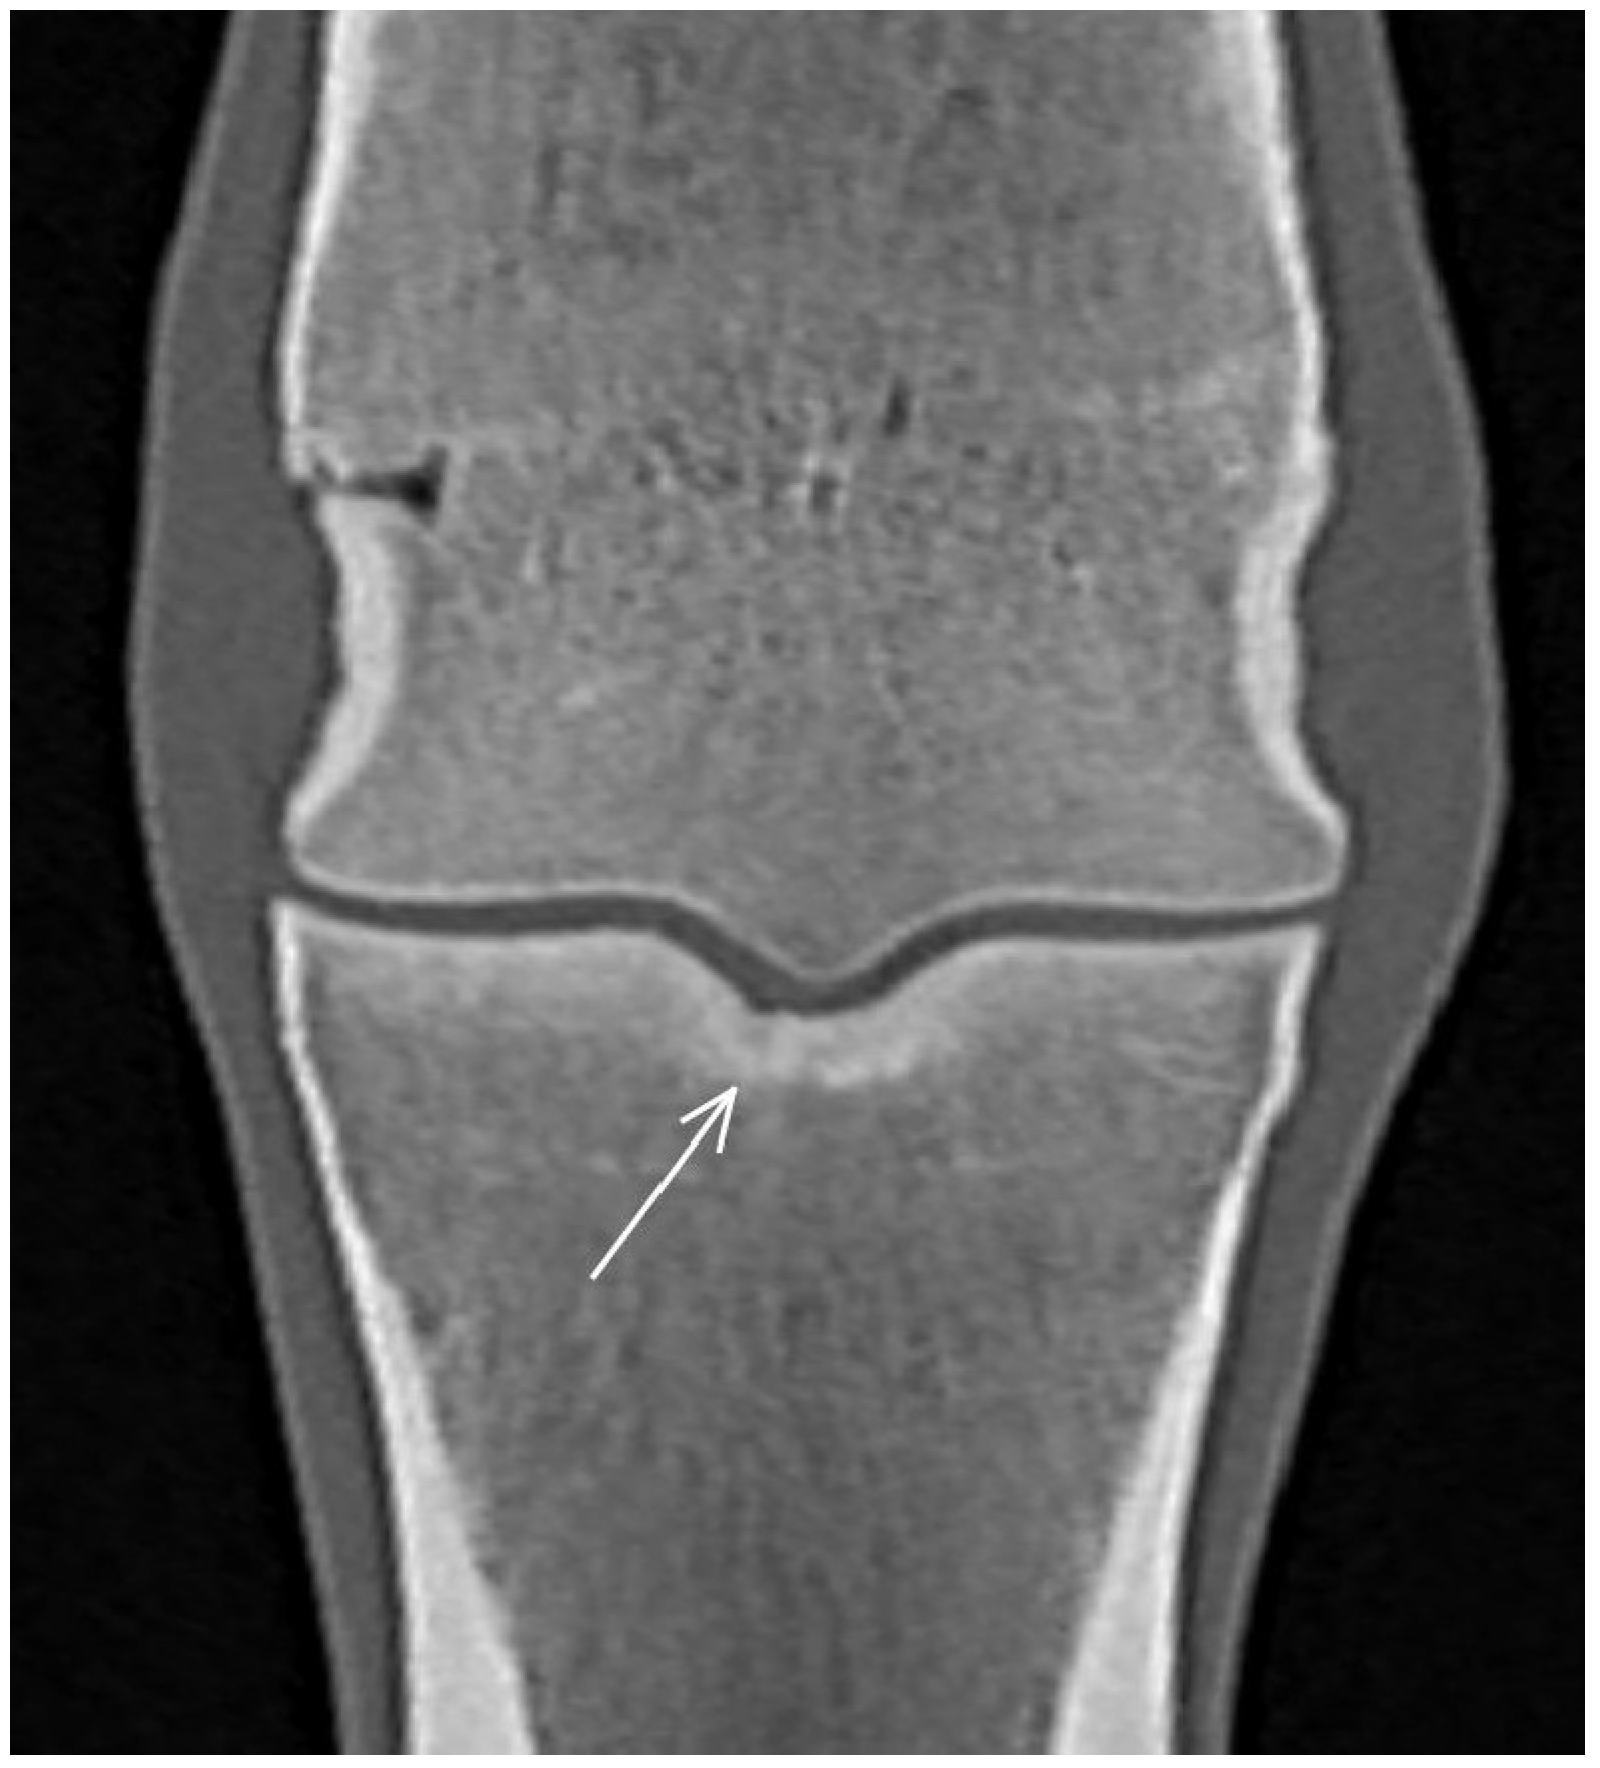

| Hypoattenuating lesion in the dorsal subchondral bone Subchondral bone thickening Dorsal/palmar half Increased attenuation in the trabecular bone Dorsal/palmar half Cone shaped/patchy Focal separated hyperattenuation | Hyperintense signal in the dorsal subchondral bone Subchondral bone thickening Dorsal/palmar half Decreased signal intensity in the trabecular bone Dorsal/palmar half Cone shaped/patchy Focal separated intermediate/low signal intensity | Radiolucent lesion Subchondral bone thickening Dorsal Increased trabecular bone opacity | |

| Proximal phalanx Sagittal groove | |||

| Subchondral bone thickening Dorsal/middle/palmar third Increased attenuation in the trabecular bone Hypoattenuating lesion in the subchondral bone Location | Subchondral bone thickening Dorsal/middle/palmar third Decreased signal intensity in the trabecular bone Increased signal intensity in the subchondral bone Location | Subchondral bone thickening Increased opacity in the trabecular bone Lucent lesion in the subchondral bone Location | |